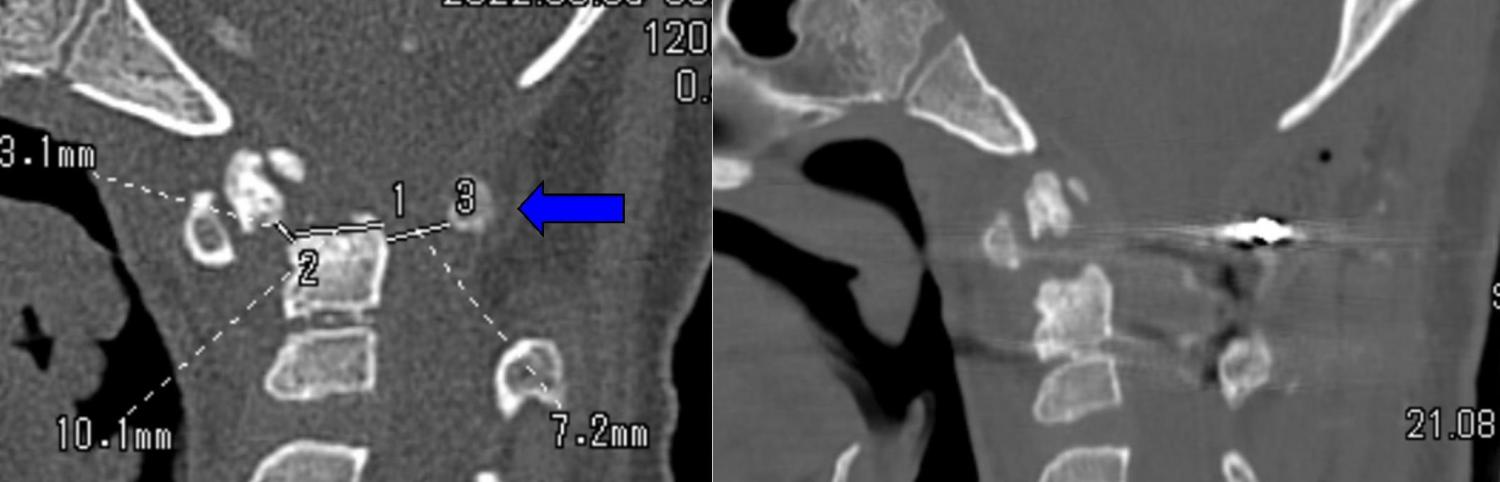

За помощью в Клинику патологии позвоночника и редких заболеваний обратились коллеги из соседнего региона. По срочным показаниям из Екатеринбурга был переведен 10-летний мальчик с вывихом первого шейного позвонка и слабостью в конечностях. При поступлении он не мог ни сидеть, не ходить.

В ускоренном порядке в Центре Илизарова ему была выполнена операция по вправлению вывиха и фиксации позвонков металлоконструкцией.

Необходимо отметить, что у мальчика есть генетическая патология: синдром Дауна, на фоне которой нестабильность и вывихи на уровне первого шейного позвонка встречаются относительно часто. Вывих произошел в повседневной жизни и без значимой травмы.